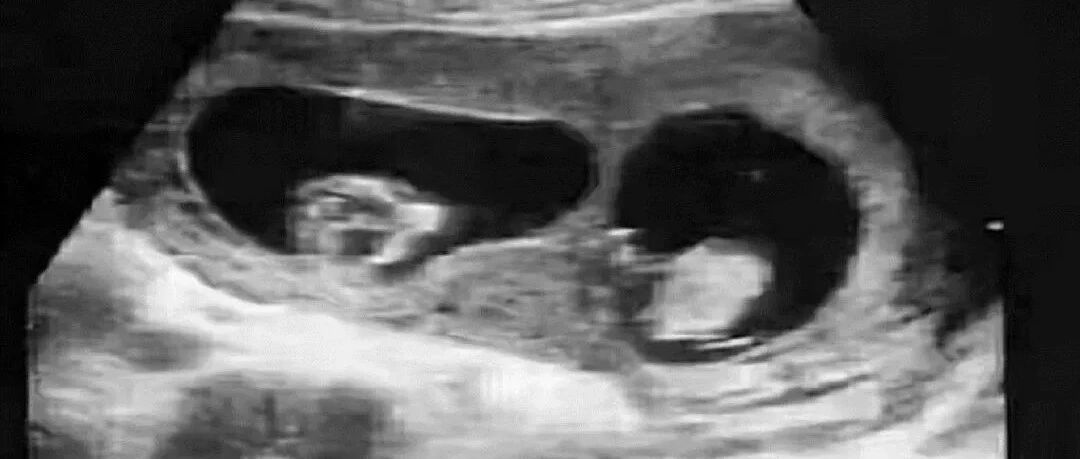

B超是诊断早期妊娠快速且准确的方法。阴道B超在末次月经后5周可见妊娠囊。6周后才能提示原始心管搏动,孕7周时才能根据有无心管搏动判断胚胎是否存活。